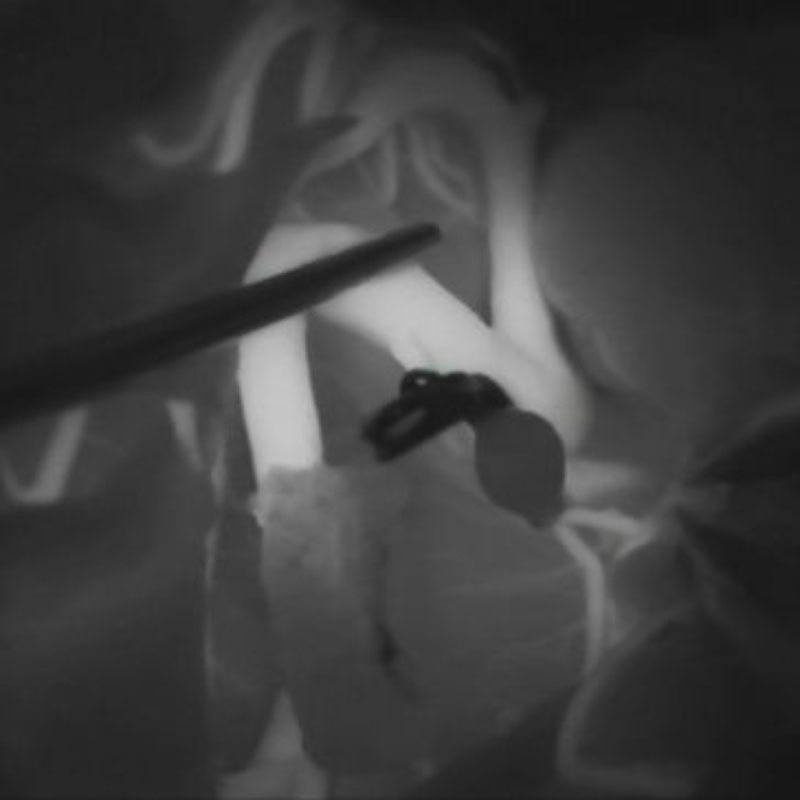

手術前

クリップ前

クリップ後

手術後